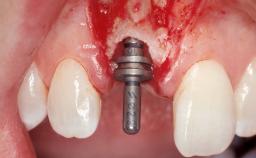

Immediate Placement of an Implant in a Maxillary Left Central Incisor Site

A 33-year-old female patient presented with an upper left central incisor that required extraction after a failed endodontic therapy. The tooth had been traumatized when the patient was a teenager and had undergone several endodontic treatments, including two apicectomy procedures. The patient was in good health and did not smoke. Clinical examination showed that the patient had a high lip line. In full smile, the gingival margins of the upper teeth were visible to the first molars. The gingival margins of central incisors 11 and 21 were only just showing. Examination of tooth 21 confirmed that the tooth was mobile and had hypererupted by 1 mm.

Placement Protocol Immediate implant placement

Tooth Site Maxillary incisor or canine

Socket Morphology Single-root socket

Socket Integrity Damage to one or more bone walls

Bone Volume Damage to one or more socket walls

Bone Augmentation Horizontal|Simultaneous

Augmentation Materials Xenogenous|Membrane

Soft Tissue Grafting Simultaneous